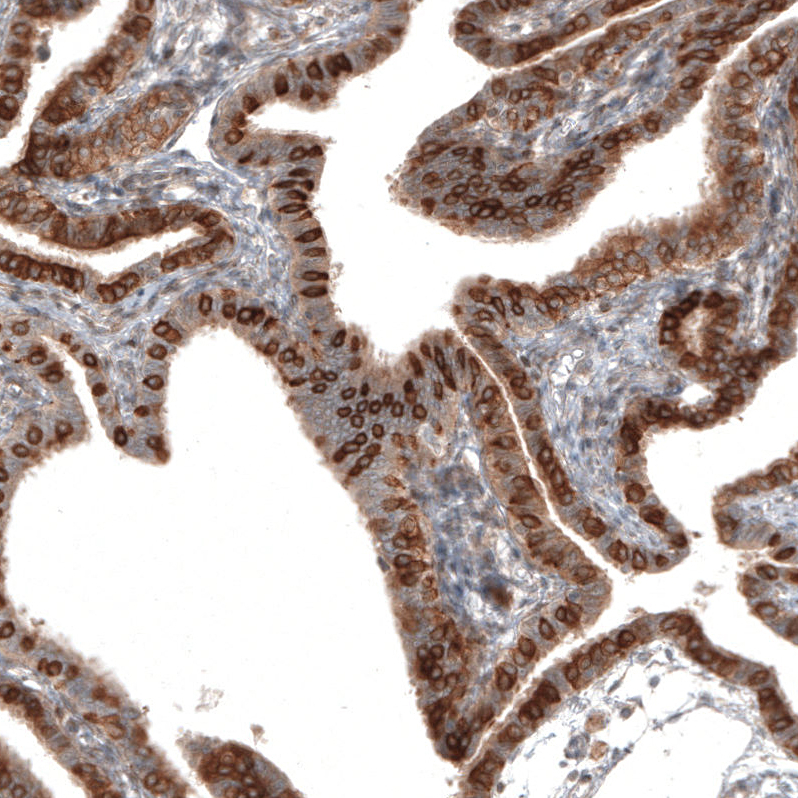

Immunohistochemical staining of human duodenum shows strong membranous positivity in glandular cells.